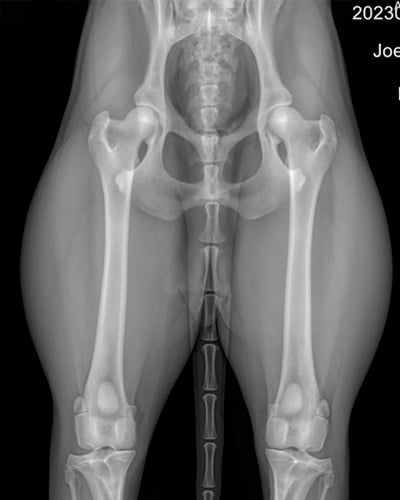

인공고관절 치환술은 골반의 관골구부분과 대퇴골의 머리부분을 인공 이식물로 대체하는 수술방법입니다.

흔히 고관절 이형성, 고관절 탈구, 골절, 퇴행성 관절염 등으로 인해 걷기 힘들고, 통증이 심하거나 일상생활이 어려운 경우 가장 최선의 선택이 THR (인공 고관절 치환술)입니다.

고관절 이형성증은 고관절이 제대로 발달하지 않아 관절의 모양이 비정상적으로 형성되고 관절염이 생기는 질환입니다. 특히 어린 시절에 고관절이 느슨하게 형성된 경우,

시간이 지나며 관절에 과도한 마찰이 생겨 수개월~수년에 걸쳐 관절염이 진행될 수 있습니다. 모든 품종에서 발생할 수 있지만, 특히 대형견에서 흔히 발생합니다.

대개 고관절이형성에서 또는 이형성 때문에 생긴 퇴행성 관절염이 있는 환자에서 실시합니다.

01사전평가 (x-ray 및 전반 건강상태 평가)